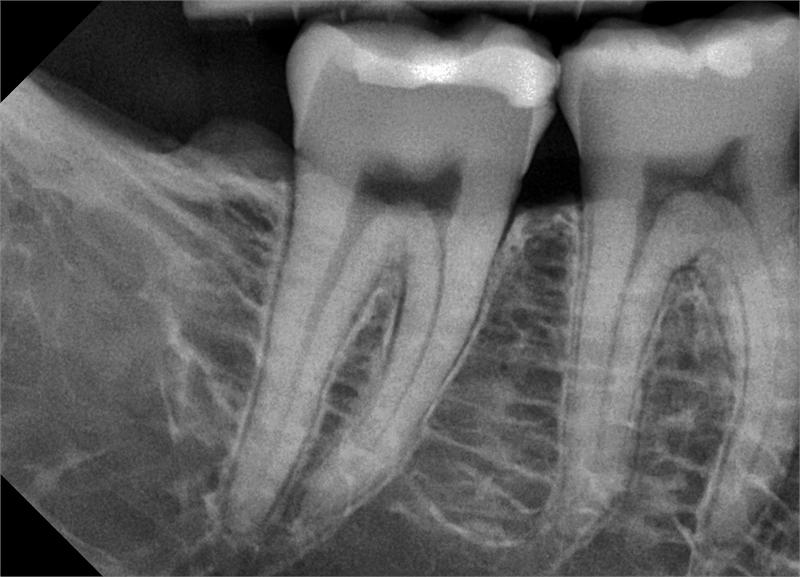

Az intraorális digitális röntgen kifejezetten egy-két fog vizsgálatára alkalmas, például gyulladt fog, gyökérkezelés vagy fogimplantátum kontrollja során. Ez a felvétel rendkívül részletgazdag képet nyújt az érintett területről, és segíti a helyes diagnózis és a megfelelő kezelési terv kialakítását.

Noha a panoráma röntgent nem helyettesíti, kiválóan kiegészíti azt – különösen akkor, ha egy adott foggal kapcsolatos kérdésre keresünk pontos választ.